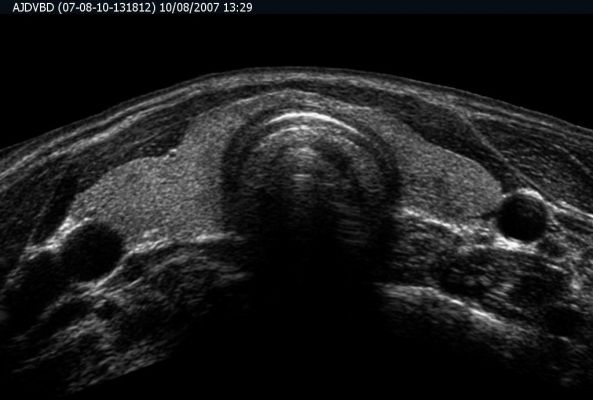

High Resolution Small Part Sonography / Musculoskeletal Sonography

All the superficial parts of the body like neck, thyroid, orbits, breast, any soft tissue swelling are best assessed on ultrasound.